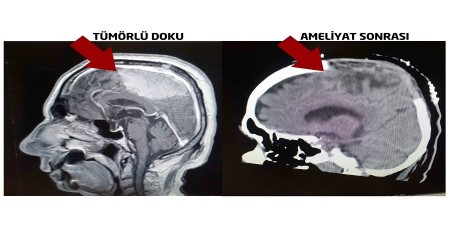

Giresun'da yaşayan Vahit Deveci, 14 yıl önce beyin tümörü nedeniyle Almanya'da ameliyat olmasına rağmen tehlikeli bölgede olması nedeniyle tümörün tamamı çıkartılamadı. Hastalık yıllar boyunca ilerledi. Yaklaşık 1 ay kadar önce ayağa kalkamayan ve yatağa mahkum hale gelen 84 yaşındaki Vahit Deveci, Medical Park Ordu Hastanesine başvurdu. Hastanede Beyin ve Sinir Cerrahisi Uzmanı Dr. Öğr. Üyesi Ahmet Eroğlu tarafından ameliyat edildi. Deveci, başarılı operasyon sonrası hayatını kabusa çeviren tümörden 30 sene sonra tamamen kurtuldu.

Dr. Öğr. Üyesi Ahmet Eroğlu operasyonla ilgili şu bilgileri verdi: "Hastamız 14 yıl önce beyin tümörü nedeniyle Almanya'da ameliyat olmuş. Beynin ana damar yapılarına yakın olan kısmı ameliyat sırasında riskli olması sebebiyle bırakılmış. Hasta yakınlarına da bu şekilde bilgi verilmiş. Alınmayan tümör gün geçtikçe büyümüş ve hastamız, durdurulamayan sara nöbetleri geçirmeye başlamış. Felç olmuş gibi ayağa kalkamayan Vahit Deveci'nin çekilen MR'ında büyük bir kitle ile karşı karşıya kaldık. Bırakılan kitle 8 cm büyümüş ve kemiğe de sıçramış. Hastanın hayati tehlikesi oldukça yüksekti. Önemli damarsal yapılara yapışıklığı söz konusuydu. Damarsal yapıların tamamından tümörü mikroskobik cerrahi eşliğinde temizledik. Yüksek riskli olan ameliyatı başarı ile gerçekleştirdik. Kontrol filmlerinde en ufak bir tümör artığına saptamadık. Hastamızı ameliyat sonrasında fizik tedavi desteği vererek şifa ile taburcu ettik."